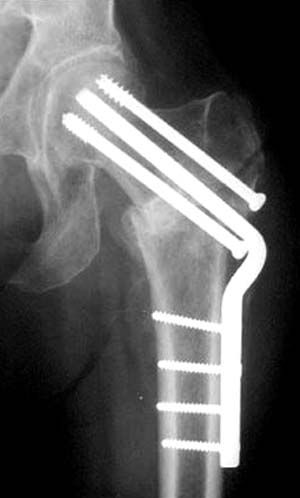

Правильная техника фиксации - это три параллельных  каннюлированных винта под углом 130 -135 градусов к диафизу, не ниже уровня малого вертеля. Проведенные ниже вертела винты с бОльшим углом (более вертикальные) в 20% осложнялись подвертельными переломами бедра. Ближе к кортикальному слою винты с длинным контактом резбовой части, а также каннюлирванные механически лучше, чем сплошные. Расположение винтово - в  в виде V т.е. один внизу по калькару и два сверху-спереди и сзади.

Для убедительности здесь пример подвертельного перелома после 3 недели, где латеральный кортекс ослаблен еще и из-за неоднократных попыток введения шурупов.

Имя     : 3 Fem neck3 wks postop.jpg

Тип     : image/jpg

Размер  : 20573 байтов

Описание: отсутствует

Url     : http://weborto.net:8080/pipermail/ortho/attachments/20120118/c4b77b39/attachment-0007.jpg